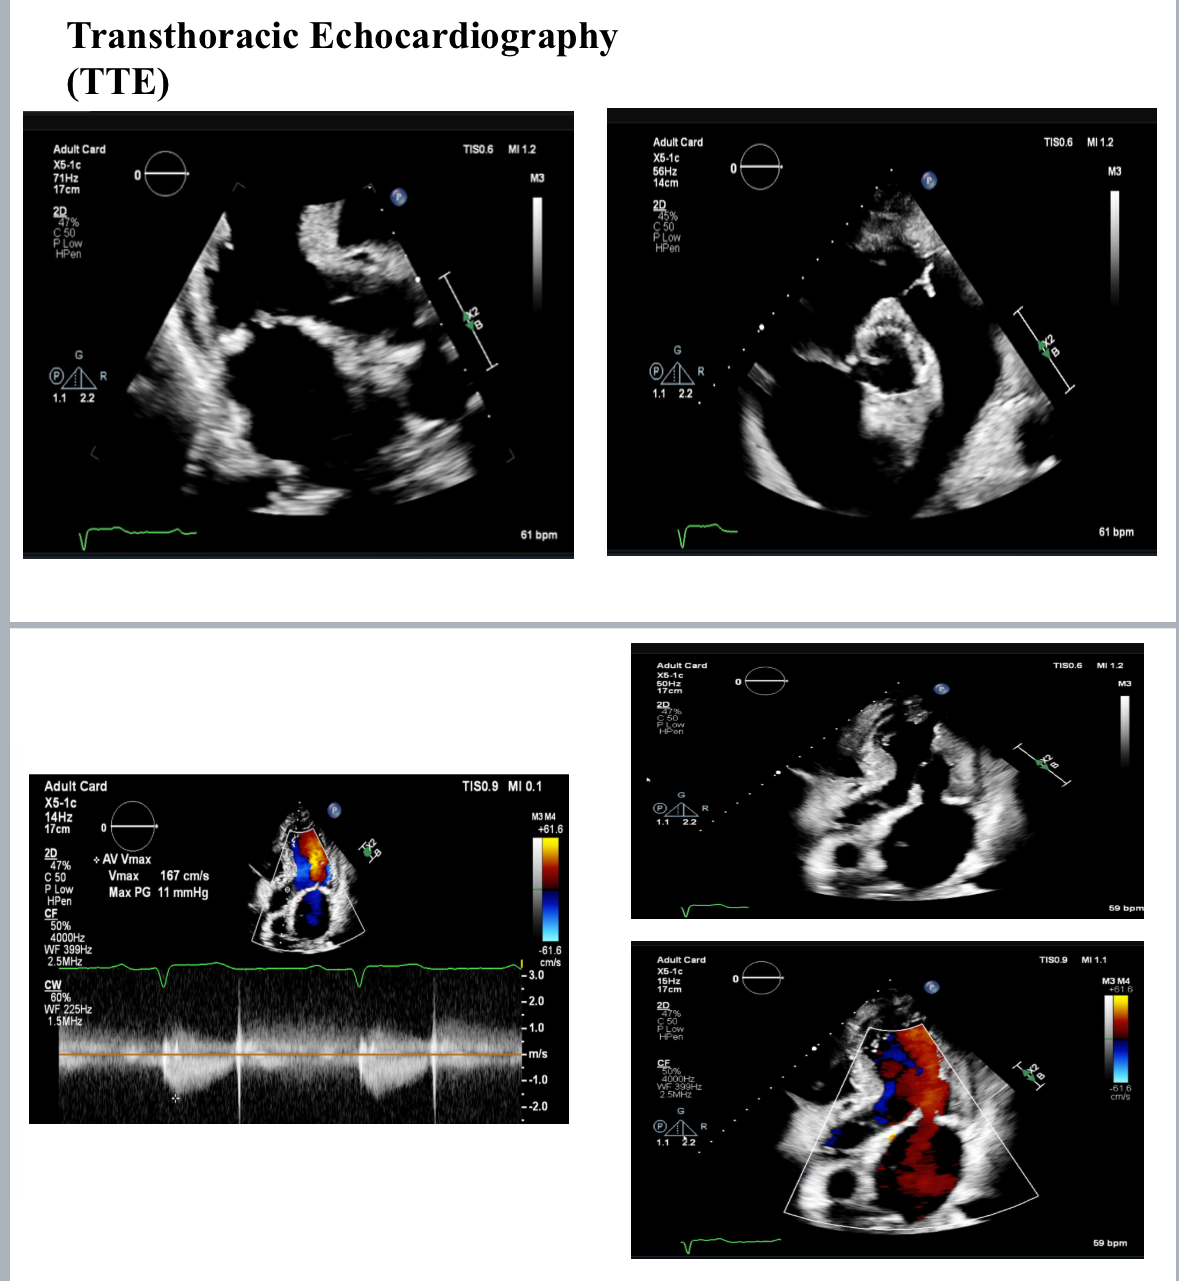

Post-TAVI aortography confirmed proper valve positioning with only a trivial paravalvular leak (PVL). The access sites were successfully closed using ProGlide and Angio-Seal devices. A total of 50 cc of Gadobutrol was used. Pre-discharge transthoracic echocardiography (TTE) confirmed good transcatheter heart valve (THV) positioning, no PVL, and a peak gradient of 6 mmHg. Renal function tests performed one week post-procedure showed no deterioration, with a creatinine level of 156 µmol/L.

Post-TAVI aortography confirmed proper valve positioning with only a trivial paravalvular leak (PVL). The access sites were successfully closed using ProGlide and Angio-Seal devices. A total of 50 cc of Gadobutrol was used. Pre-discharge transthoracic echocardiography (TTE) confirmed good transcatheter heart valve (THV) positioning, no PVL, and a peak gradient of 6 mmHg. Renal function tests performed one week post-procedure showed no deterioration, with a creatinine level of 156 µmol/L.